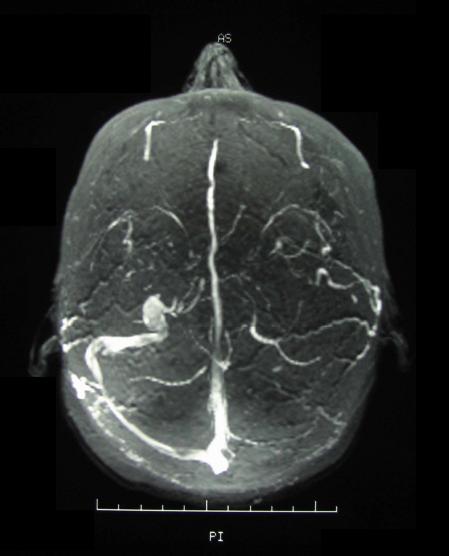

신경베체트병으로 불리는 중추신경계(CNS) 침범은 만성 수막뇌염으로 가장 자주 발생한다. 병변은 뇌간, 기저핵 및 반구 심부 백질에서 발생하며, 다발성 경화증과 유사할 수 있다.

신경학적 침범은 무균성 수막염에서 경막 정맥동 혈전증과 같은 혈관 혈전증, 혼란, 발작, 기억 상실을 나타내는 유기적 뇌 증후군에 이르기까지 다양하다. 갑작스러운 청력 손실(감각신경성)이 동반되기도 한다.[4]

급성 시신경병증이 있는 일부 환자에서 자기 공명 영상(MRI)에서 시신경 조영 증강이 확인될 수 있다. 그러나 정상적인 검사 결과가 시신경병증을 배제하지는 않는다. 뇌척수액(CSF) 분석은 백혈구 증가증 유무에 관계없이 단백질 수치 상승을 나타낼 수 있다. 두개 내 고혈압 및 시신경 위축의 원인으로 경막 정맥동 혈전증을 식별하기 위해 혈관 조영술을 포함한 영상 검사가 필요할 수 있다.